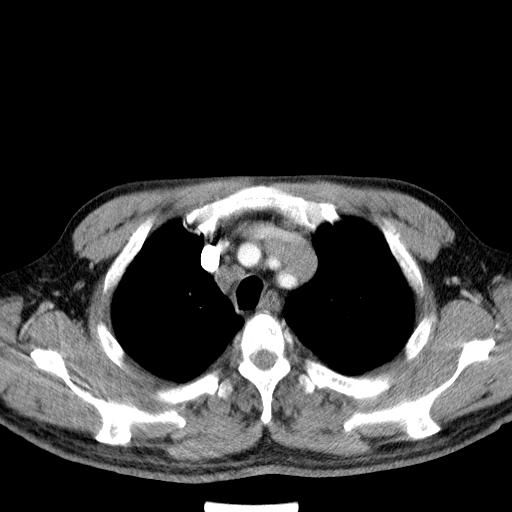

先行ct平扫,纵膈内多发软组织影,ct值约为36hu,以下为增强扫描和腹部平扫。

请会诊